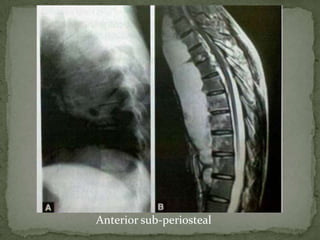

Anterior Subperiosteal –

 begins at the anterior vertebral margin underneath the

periosteum

 spreads beneath the ALL

 subtle anterior erosions of multiple vertebrae

 clinical symptoms are severe in relation to the minor

radiographic abnormalities

 Disk destruction maybe late and anterior erosions are

difficult to detect on plain radiographs.

Anterior sub-periosteal